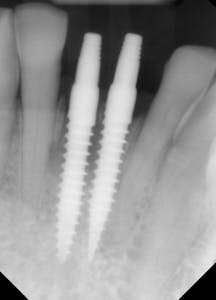

This patient presented with discomfort and mobile teeth Nos. 24 and 25. Extractions were performed, and the area was allowed to heal for six months. Mini-implants were placed in site Nos. 24 and 25 and immediately loaded with temporary crowns. The final splinted restoration was cemented two weeks later.

Figure 8: Initial implant placement DIO 3.0 x 16 mm implants

Figure 9: Implants restored two weeks after placement